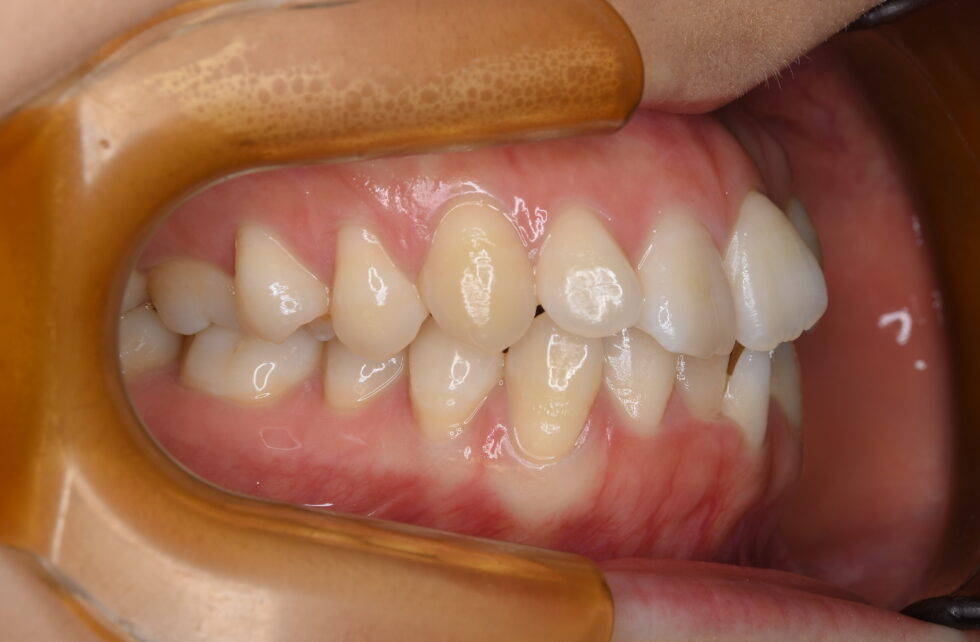

初診時年齢24歳の女性 上下顎前歯部叢生を主訴として来院された。数年前にも当院にご相談に来院されたが、中学生時で永久歯の抜歯に難色を示されたため見送ったとのことであった。

上顎左側側切歯が口蓋側転位となり右側第一大臼歯が口蓋側へ転位していた。下顎は左側中切歯、側切歯が唇舌的に重なり合っていた。叢生の状態に加え下顎が左側へ偏位して臼歯部は左下が内側へ極端に傾斜していた。上顎左右側第一小臼歯、下顎は正中のずれを補うように右側を第一小臼歯、左側は第二小臼歯を抜歯していただき上下顎舌側マルチブラケット装置を使用して動的治療を行った。臼歯部の頬舌的な傾斜を調整しながら咬合を適正化するのに時間を要した。仕事上、来院間隔が長くなる傾向があったため動的治療期間は3年5か月間を要した。 調整来院は27回であった。治療費の目安140万円程度